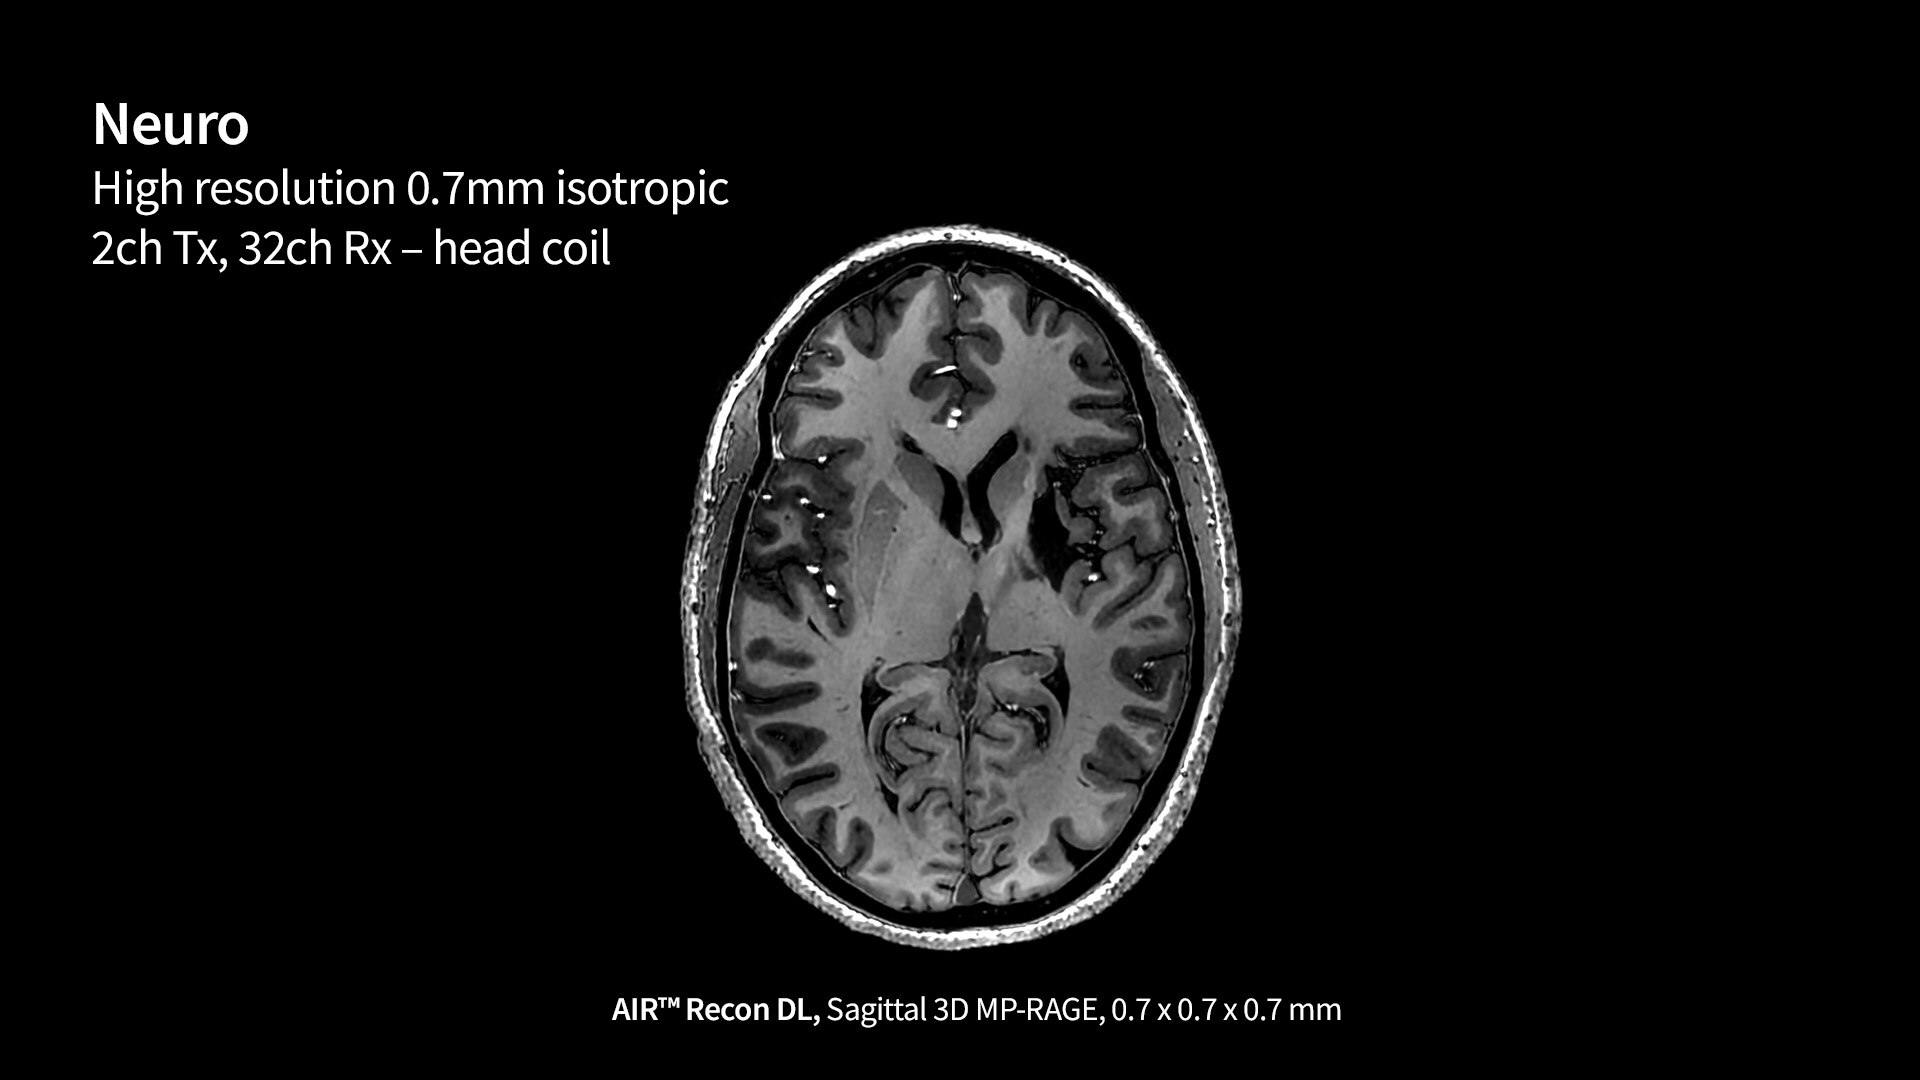

ÉVALUATION DE LA FONCTION CARDIAQUE FŒTALE

Aller au cœur du problème

L’identification précoce des anomalies cardiaques fœtales permet d'intervenir plus tôt, de planifier l’accouchement, et éventuellement d’améliorer les résultats cliniques. Le Voluson Expert 22 procure une solution complète d'outils évolutifs, pour aider à distinguer les structures les plus minuscules avec une clarté étonnante, afin de fournir des réponses plus rapidement aux patientes.

« Le Voluson Expert 22 est très utile pour évaluer la fonction cardiaque fœtale. Lorsque vous utilisez fetalHQ, il est difficile d'identifier clairement le contour endocardique des 4 cavités cardiaques. Radiant permet d’obtenir une image plus claire et d’identifier plus précisément le contour endocardique pour le traçage. L'imagerie 2D s’est considérablement améliorée, ce qui rend l’évaluation avec fetalHQ encore plus précise. »

Dr Greggory DeVore

Fetal Diagnostic Center - Californie, États-Unis